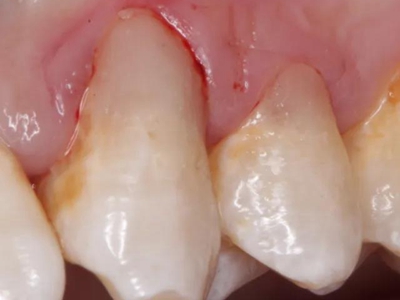

酸蚀症牙齿有黄斑图

酸蚀症可导致患者靠近牙根处有偏黄褐色的黄斑,形状不规则,质地较软,易崩碎而逐级形成实质性缺损,需保持口腔卫生,进行劳动保护。